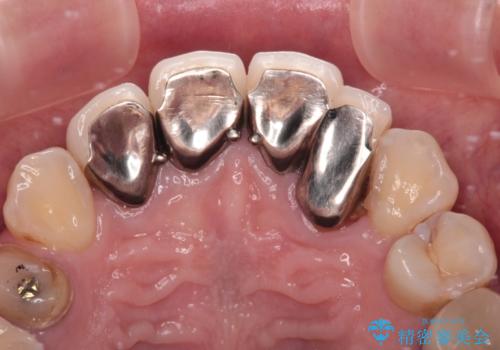

むし歯で神経を取り除いたことをきっかけに、前歯をセラミックにしたそうですが、金属の縁が見えてきたり、内側に引っ込んでいた歯を強引に前に出しことで汚れが溜まったりと、不具合を感じているとのことでした。

結婚式が近いことから、前歯は舌側に転位している歯は抜歯してブリッジにすることで外見と清掃性を改善し、速やかにオールセラミッククラウンにて補綴治療を行うこととしました。